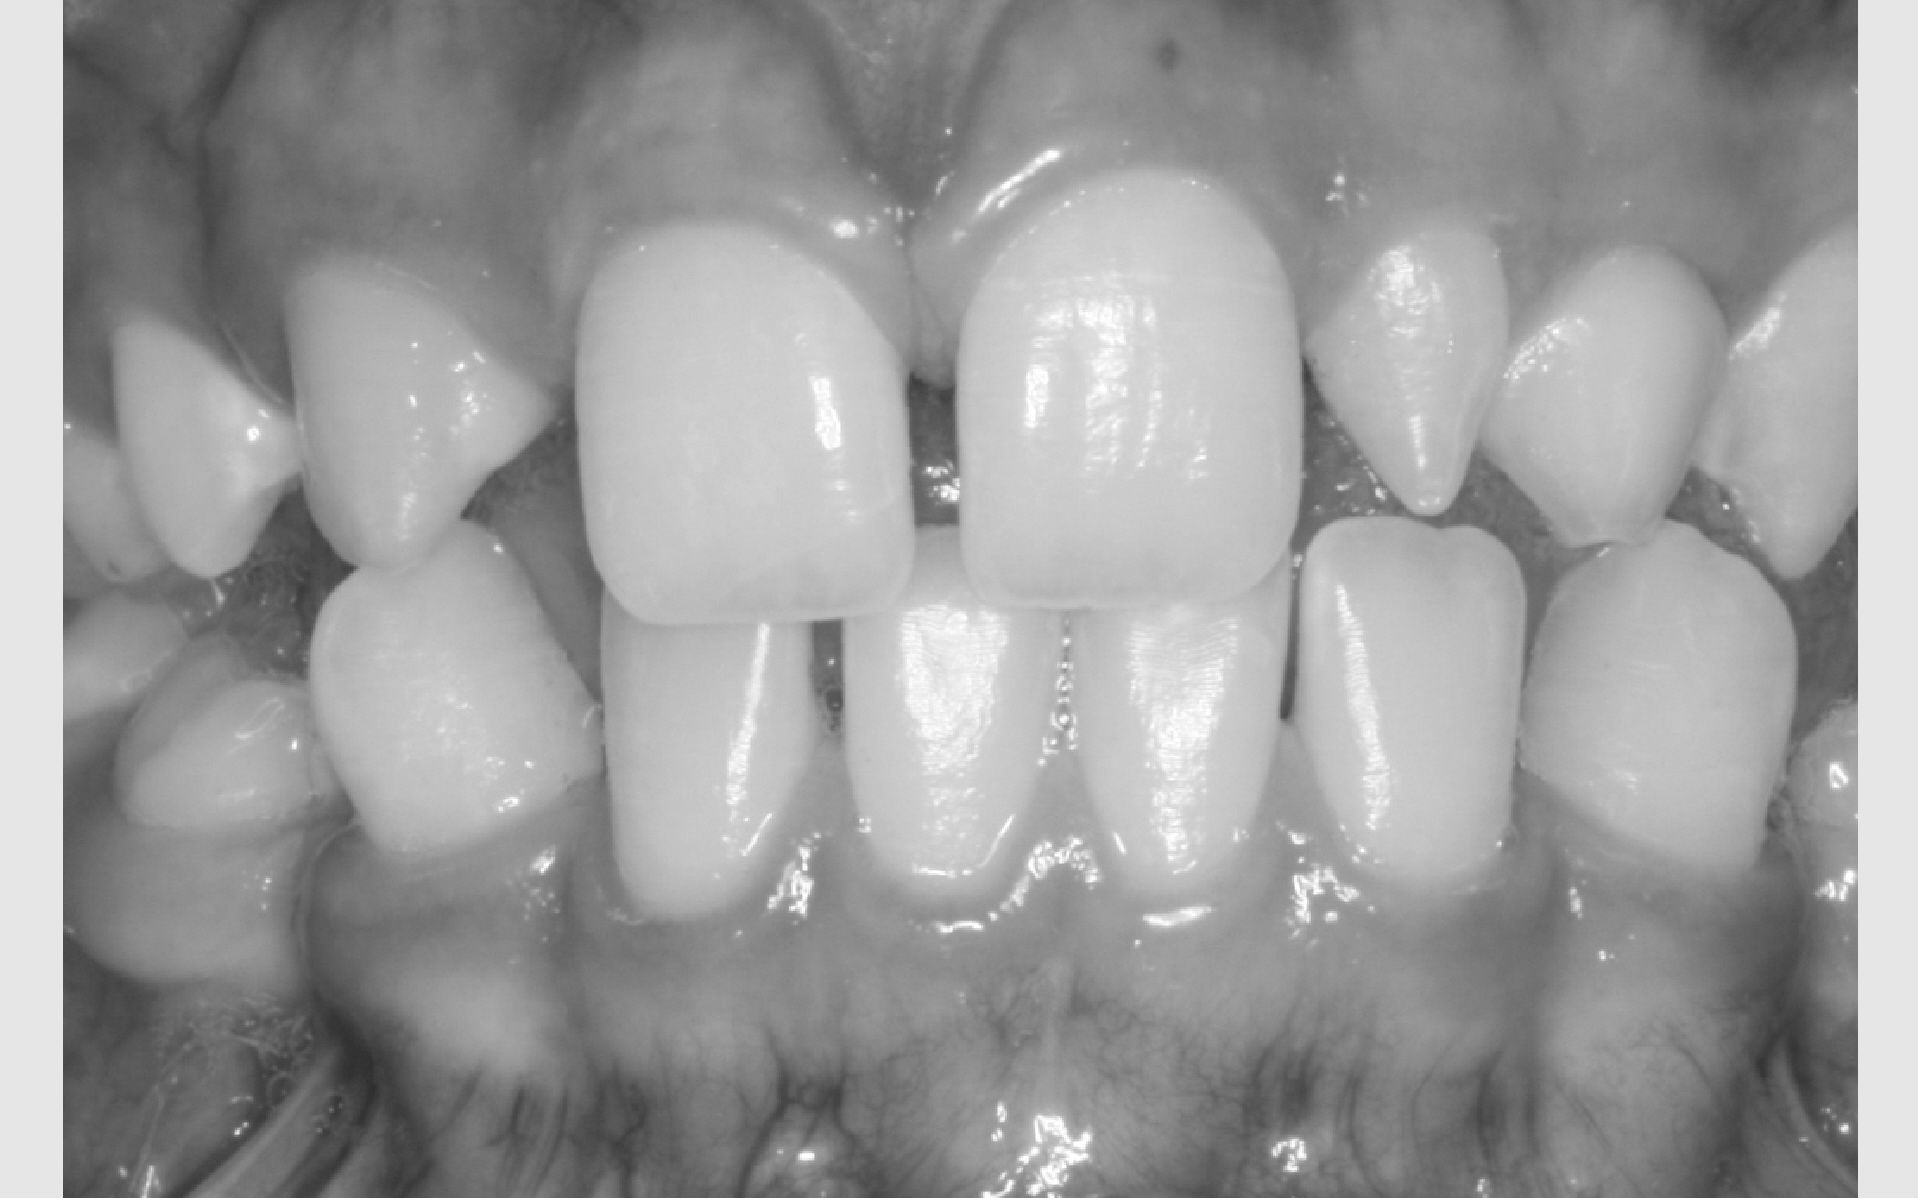

Der kan være forskellige grunde til, at et barn eller en ung får tilbudt bøjlebehandling. De hyppigste grunde er:

• Misforhold mellem kæber: stort overbid eller underbid

• Ekstrem pladsmangel

• Fejllejrede tænder, der giverrisiko for skader på andre tænder

Hver gang dit barn bliver undersøgt i Tandplejen, bliver der taget stilling til, hvordan biddet fungerer. Hvis der ses uregelmæssigheder, bliver dit barn undersøgt af en specialtandlæge på den klinik, I er vant til at komme på.

Vurderer specialtandlægen, at en tandreguleringsbehandling muligvis kan gavne dit barn, inviteres I til en større undersøgelse på Tandreguleringsklinikken, Filstedvej 10 i Vejgaard.